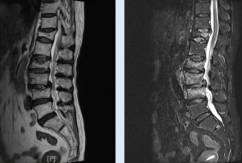

Case 3: 62-year-old postmenopausal female with vertebral fracture

Romosozumab ➝ Denosumab